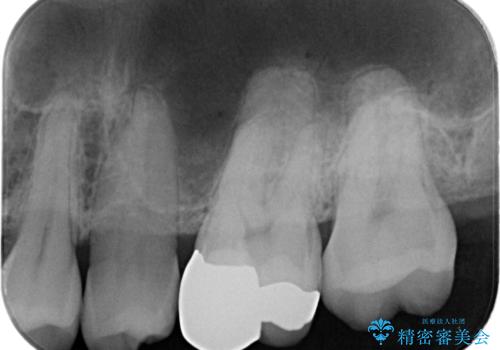

- 歯が欠けたとのことで来院された患者様です。

1本はゴールドアンレー、もう1本はセラミックインレーで修復します。

- 左上6/ゴールドアンレー:110,000円 左上7/セラミックインレー:77,000円費用は治療当時の料金となります

患者様の咬む力や削るべき歯の量によって、使用する材料を決めております。